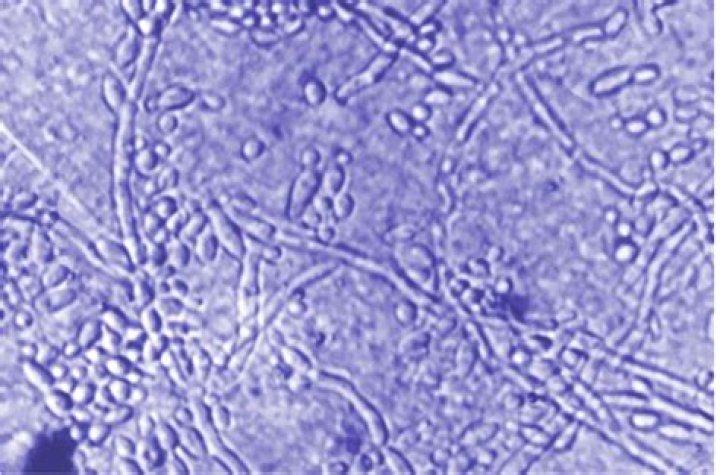

Yeasts. Yeasts are fungi that grow as single cells, producing daughter cells either by budding (the budding yeasts) or by binary fission (the fission yeasts). the dimorphic fungus Candida albicans which can be a significant pathogen of humans. some of the common leaf surface yeasts.

Secondly, what is Pseudohyphae in Candida? Pseudohyphae are a distinct growth form that differs from both yeast cells and parallel-sided hyphae and are characterized by synchronously dividing elongated yeast cells (5, 7, 41, 42).

albicans can take on either a unicellular (yeast) or multicellular (hyphae, pseudohyphae) form. The yeast form is 10-12 microns across, and is Gram-positive. A transcription repressor is needed to maintain the yeast state.